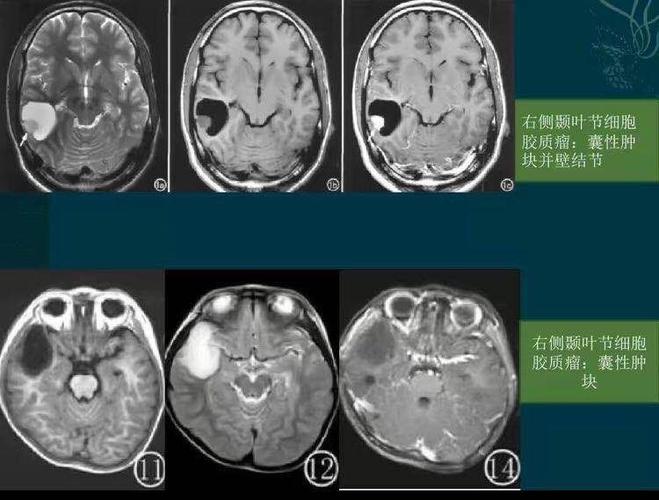

二,影像表现:右颞叶海马区占位性病变,ct呈略高密度,t1wi呈低信号